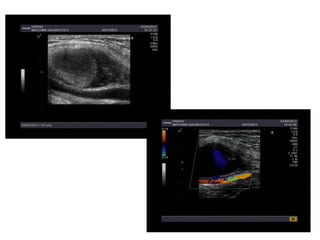

Axillary artery pseudoaneurysm

- 1.

USG GUIDED GRADEDCOMPRESSION

FOR

AXILLARY ARTERY PSUEDOANEURYSM

DR HEMANT DESHMUKH

DR AMOL BHALEKAR